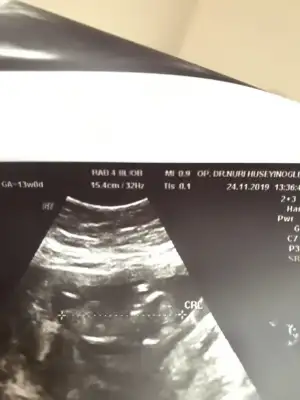

Usg yine aynı netlik yok 11 yada 12 haftanızda tekrar paylaşın 10+3 de nub iki tarafa benziyor o nedenle 11 yada 12 hafta usg istedimYordum sizi ama bu fotoyla bakarmısınız çok merak ediyorumda

Usg kaç haftalık sanki kız net degil usg başka varmımerhaba bende çok merak ettim yorumlar mısınız acaba :)

tam 10.hafta merakımdan dayanamayıp yolladım :)Usg kaç haftalık sanki kız net degil usg başka varmı

11 yada 12 olmalı 10. haftada nub iki tarafa benzer ama şimdilik diyorum kız sanki tekrar usg paylaşıntam 10.hafta merakımdan dayanamayıp yolladım :)

KızIkra meyra Merhaba 11+3 ultrason resmini yorumlarmisiniz

KızMerhaba benim minigimede yorum 11.5 haftalık

Kız diyorumYordum sizi ama bu fotoyla bakarmısınız çok merak ediyorumda

Kız13+1 doktorumuz göstermedi dedi cinsiyetini rica etsem tahminde bulunurmusunuz